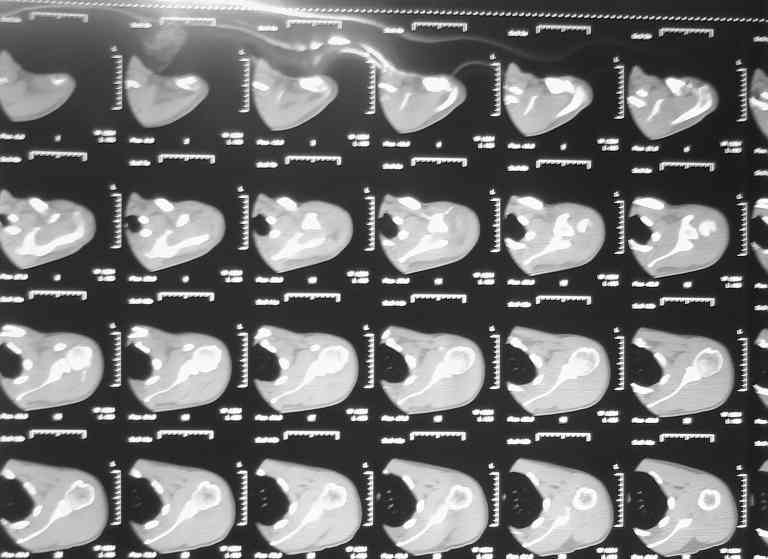

плечо в наружной ротации (см. фото). Сделали Кт (На серии КТ с толщиной

срезов 3 мм в левой плечевой кости определяется отрыв большого бугорка,

определяется линейный перелом клювовидного отростка левой лопатки без

смещения отломков (стрелки). В полости сустава- небольшое количество

жидкости. В головке плечевой кости определяется эностоз. Определяется

краевые костные разрастания акромиального конца ключицы. Заключение:

перелом левой лопатки и плечевой кости.) Возникли вопросы по дальнейшей